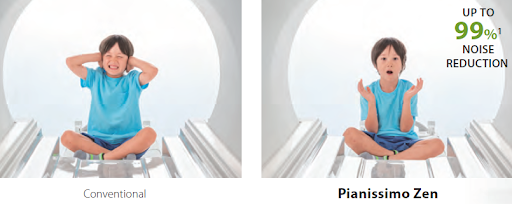

Теперь возможно проведение МРТ-исследования с большим комфортом для пациента. Исследование проводится практически бесшумно благодаря технологии Pianissimo и Pianissimo Zen.

Технология Pianissimo и Pianissimo Zen сокращают шум до 99%, что делает обследование еще более комфортными и простым для проведения. Пациенты могут быть расслабленными и спокойными.